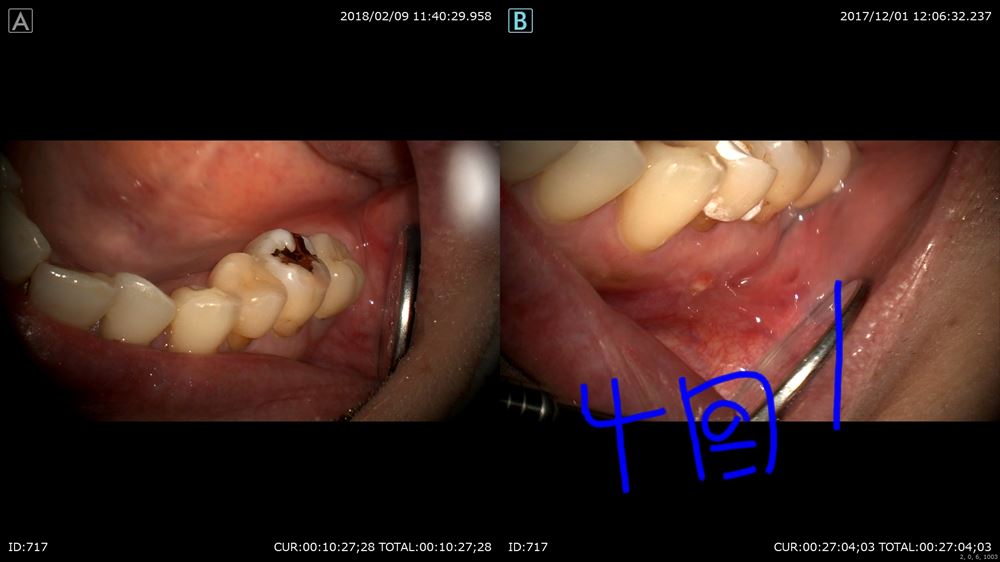

重症の虫歯で11月 右 今日 左

キチンと治療すれば腫れも引き歯を残せます。

やはり膿んでる。右 今日 左 12月

治療は被せ物まで4回。

今日で終わり。お母さんまたメンテナンス来てください。

この様に術前 右 術後 左

見て頂き喜んでいました。